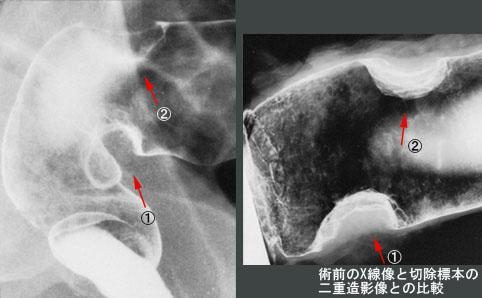

具有两处分别表现为台状变形和弧状变形的大肠癌病变的病例

[ Image ID:8987 ]

恶性上皮性肿瘤/腺癌

部位(按器官分)

大肠/直肠

肿瘤的肉眼分类

2型(溃疡局限型)/

肿瘤最大直径

25~29

肿瘤的深度